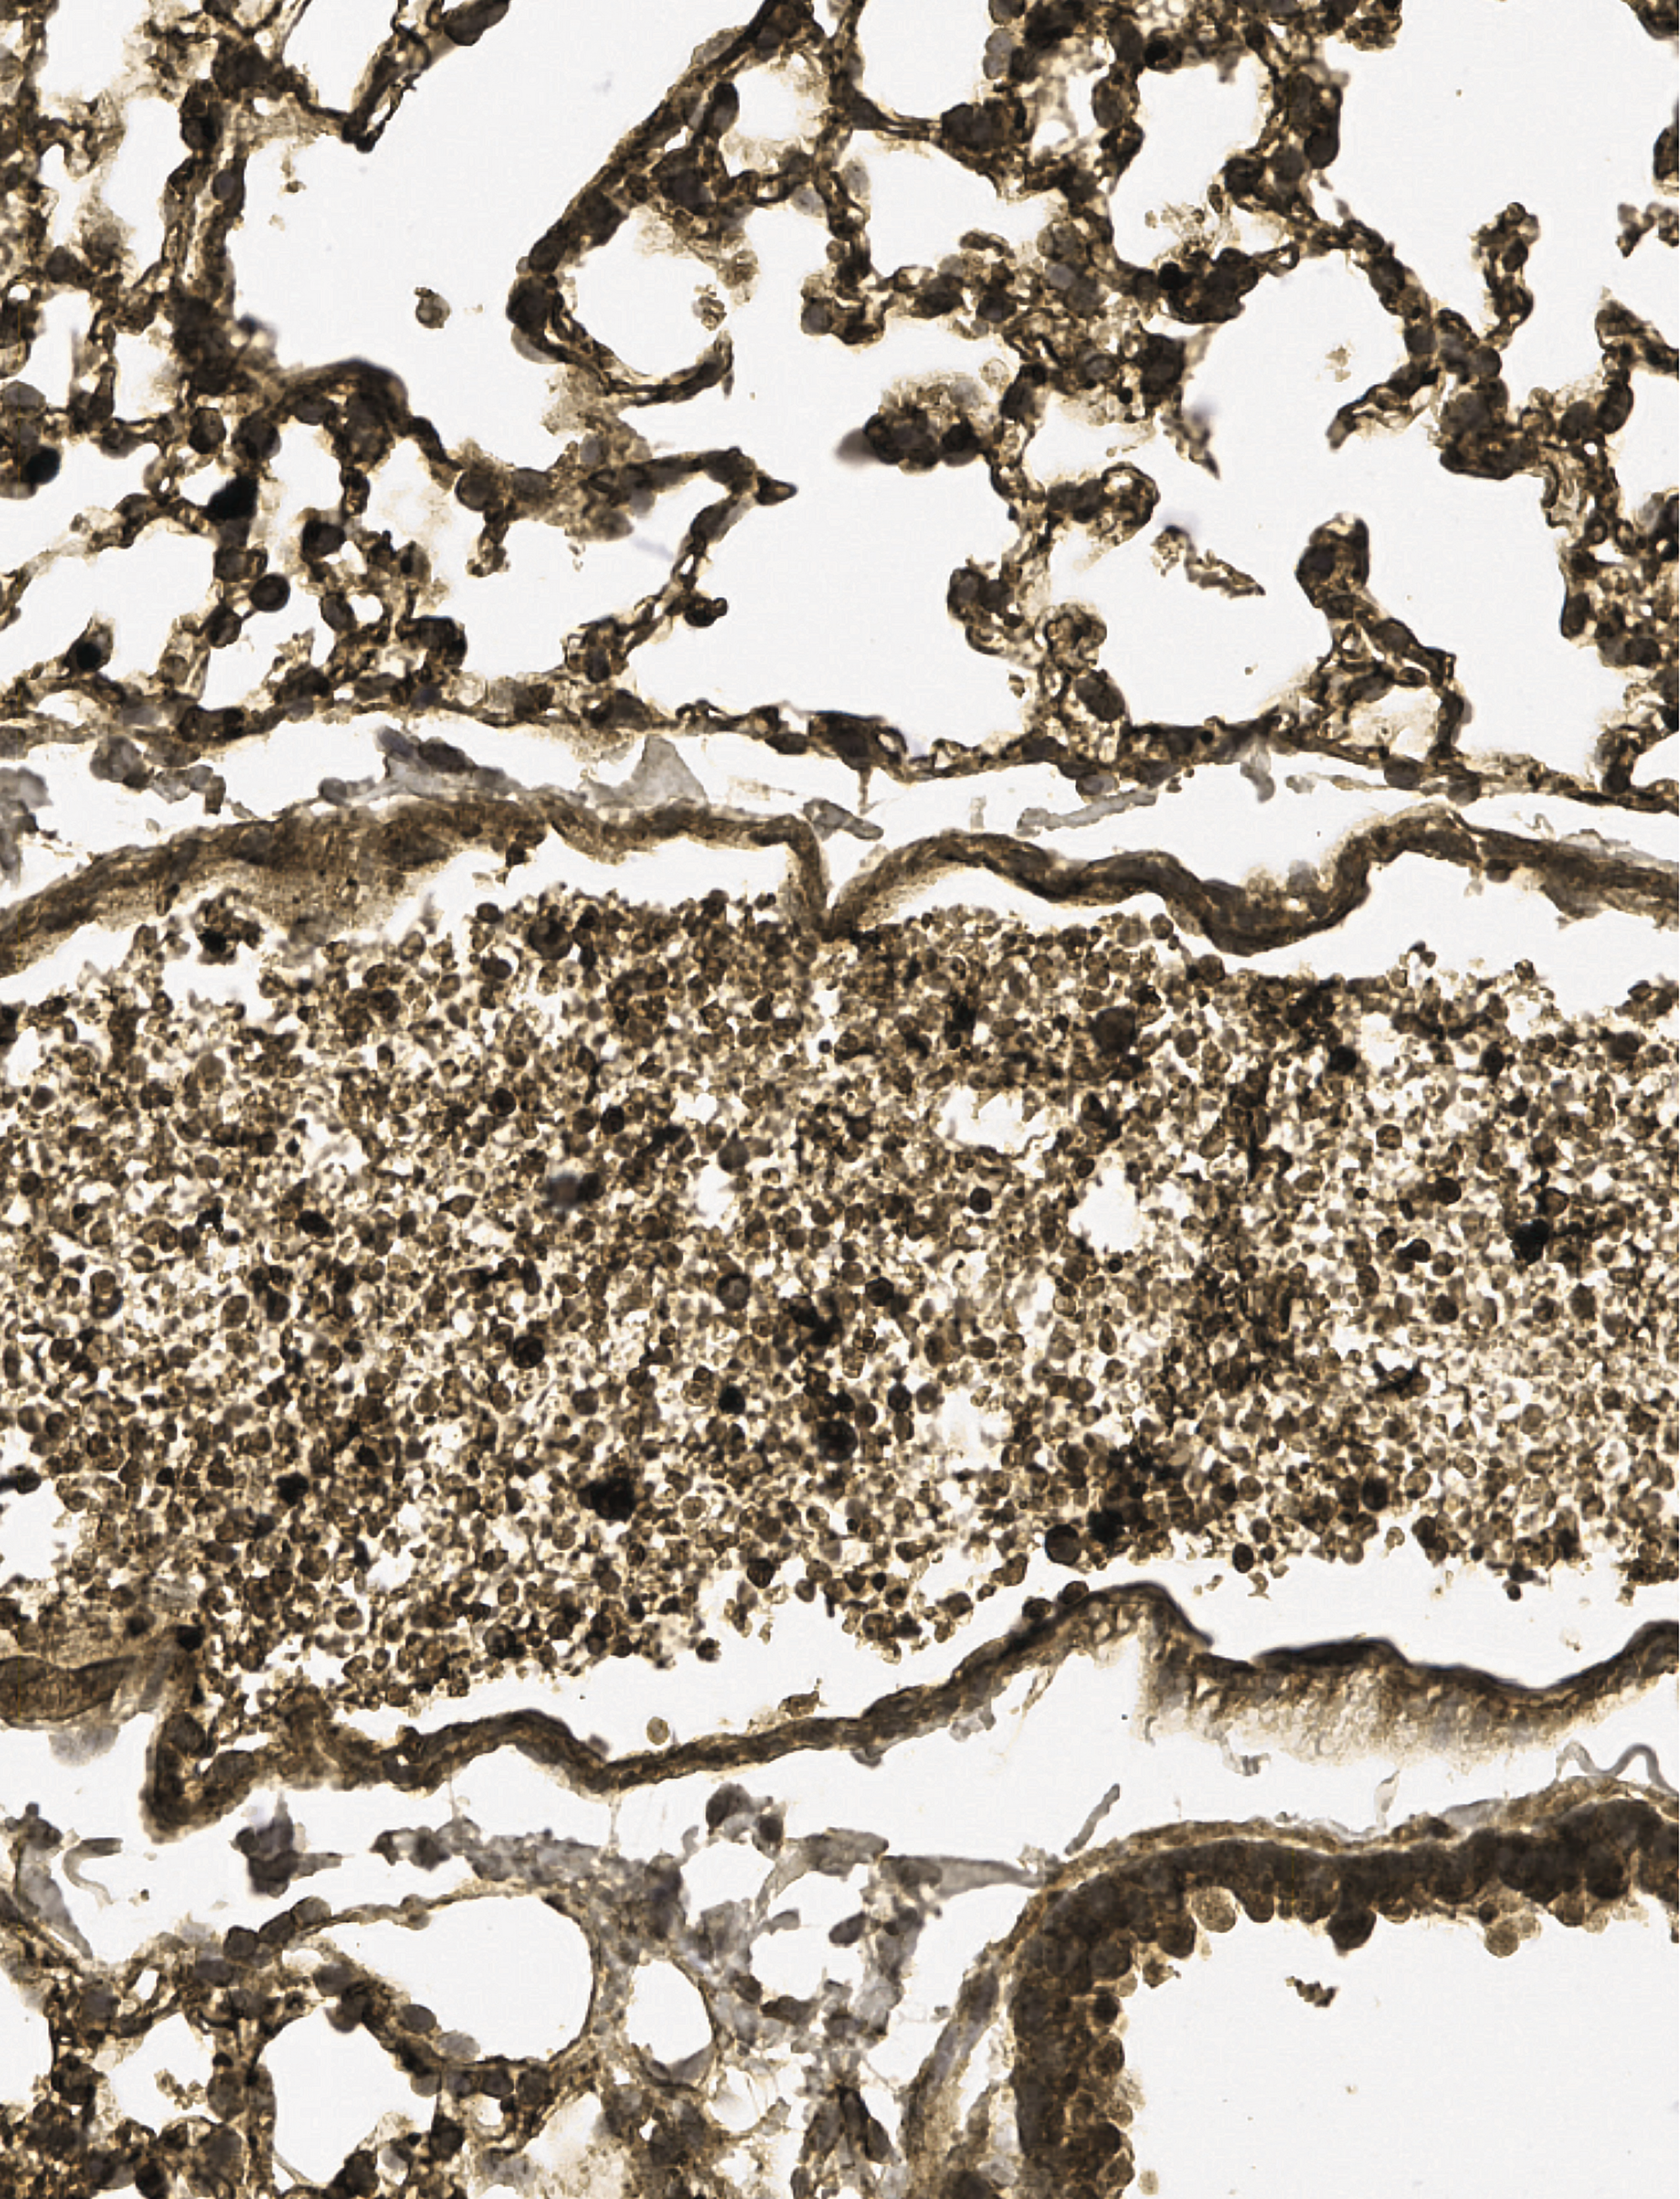

An image of the lung of a mouse with severe α-thalassemia shows fibrinogen-rich vascular occlusion. These mice exhibit symptoms of diffuse microvascular occlusion, including high plasma D-dimer, elevated respiratory rates, and symptoms of ischemic stroke, including spinning and limb paralysis. See the article by Chappell et al on page 1633.

α-Thalassemia (AT) is a commonly occurring hemoglobinopathy related to deletion of α-globin genes. Severe AT reflects deletion of 3 or 4 of the α-globin genes and is associated with severe hemolytic anemia or prenatal mortality, respectively. AT has been difficult to study because of the absence of mouse models. Chappell et al have created a model of severe AT via lipid nanoparticle delivery targeting stem cells with a Cre messenger RNA, leading to deletion of α-globin genes and transplanting transduced stem cells into adult mice. Delivery of a lentiviral α-globin gene ameliorates the disease. These studies provide an important model of AT, while the efficacy of nanoparticle transduction offers hope for in vivo transduction.